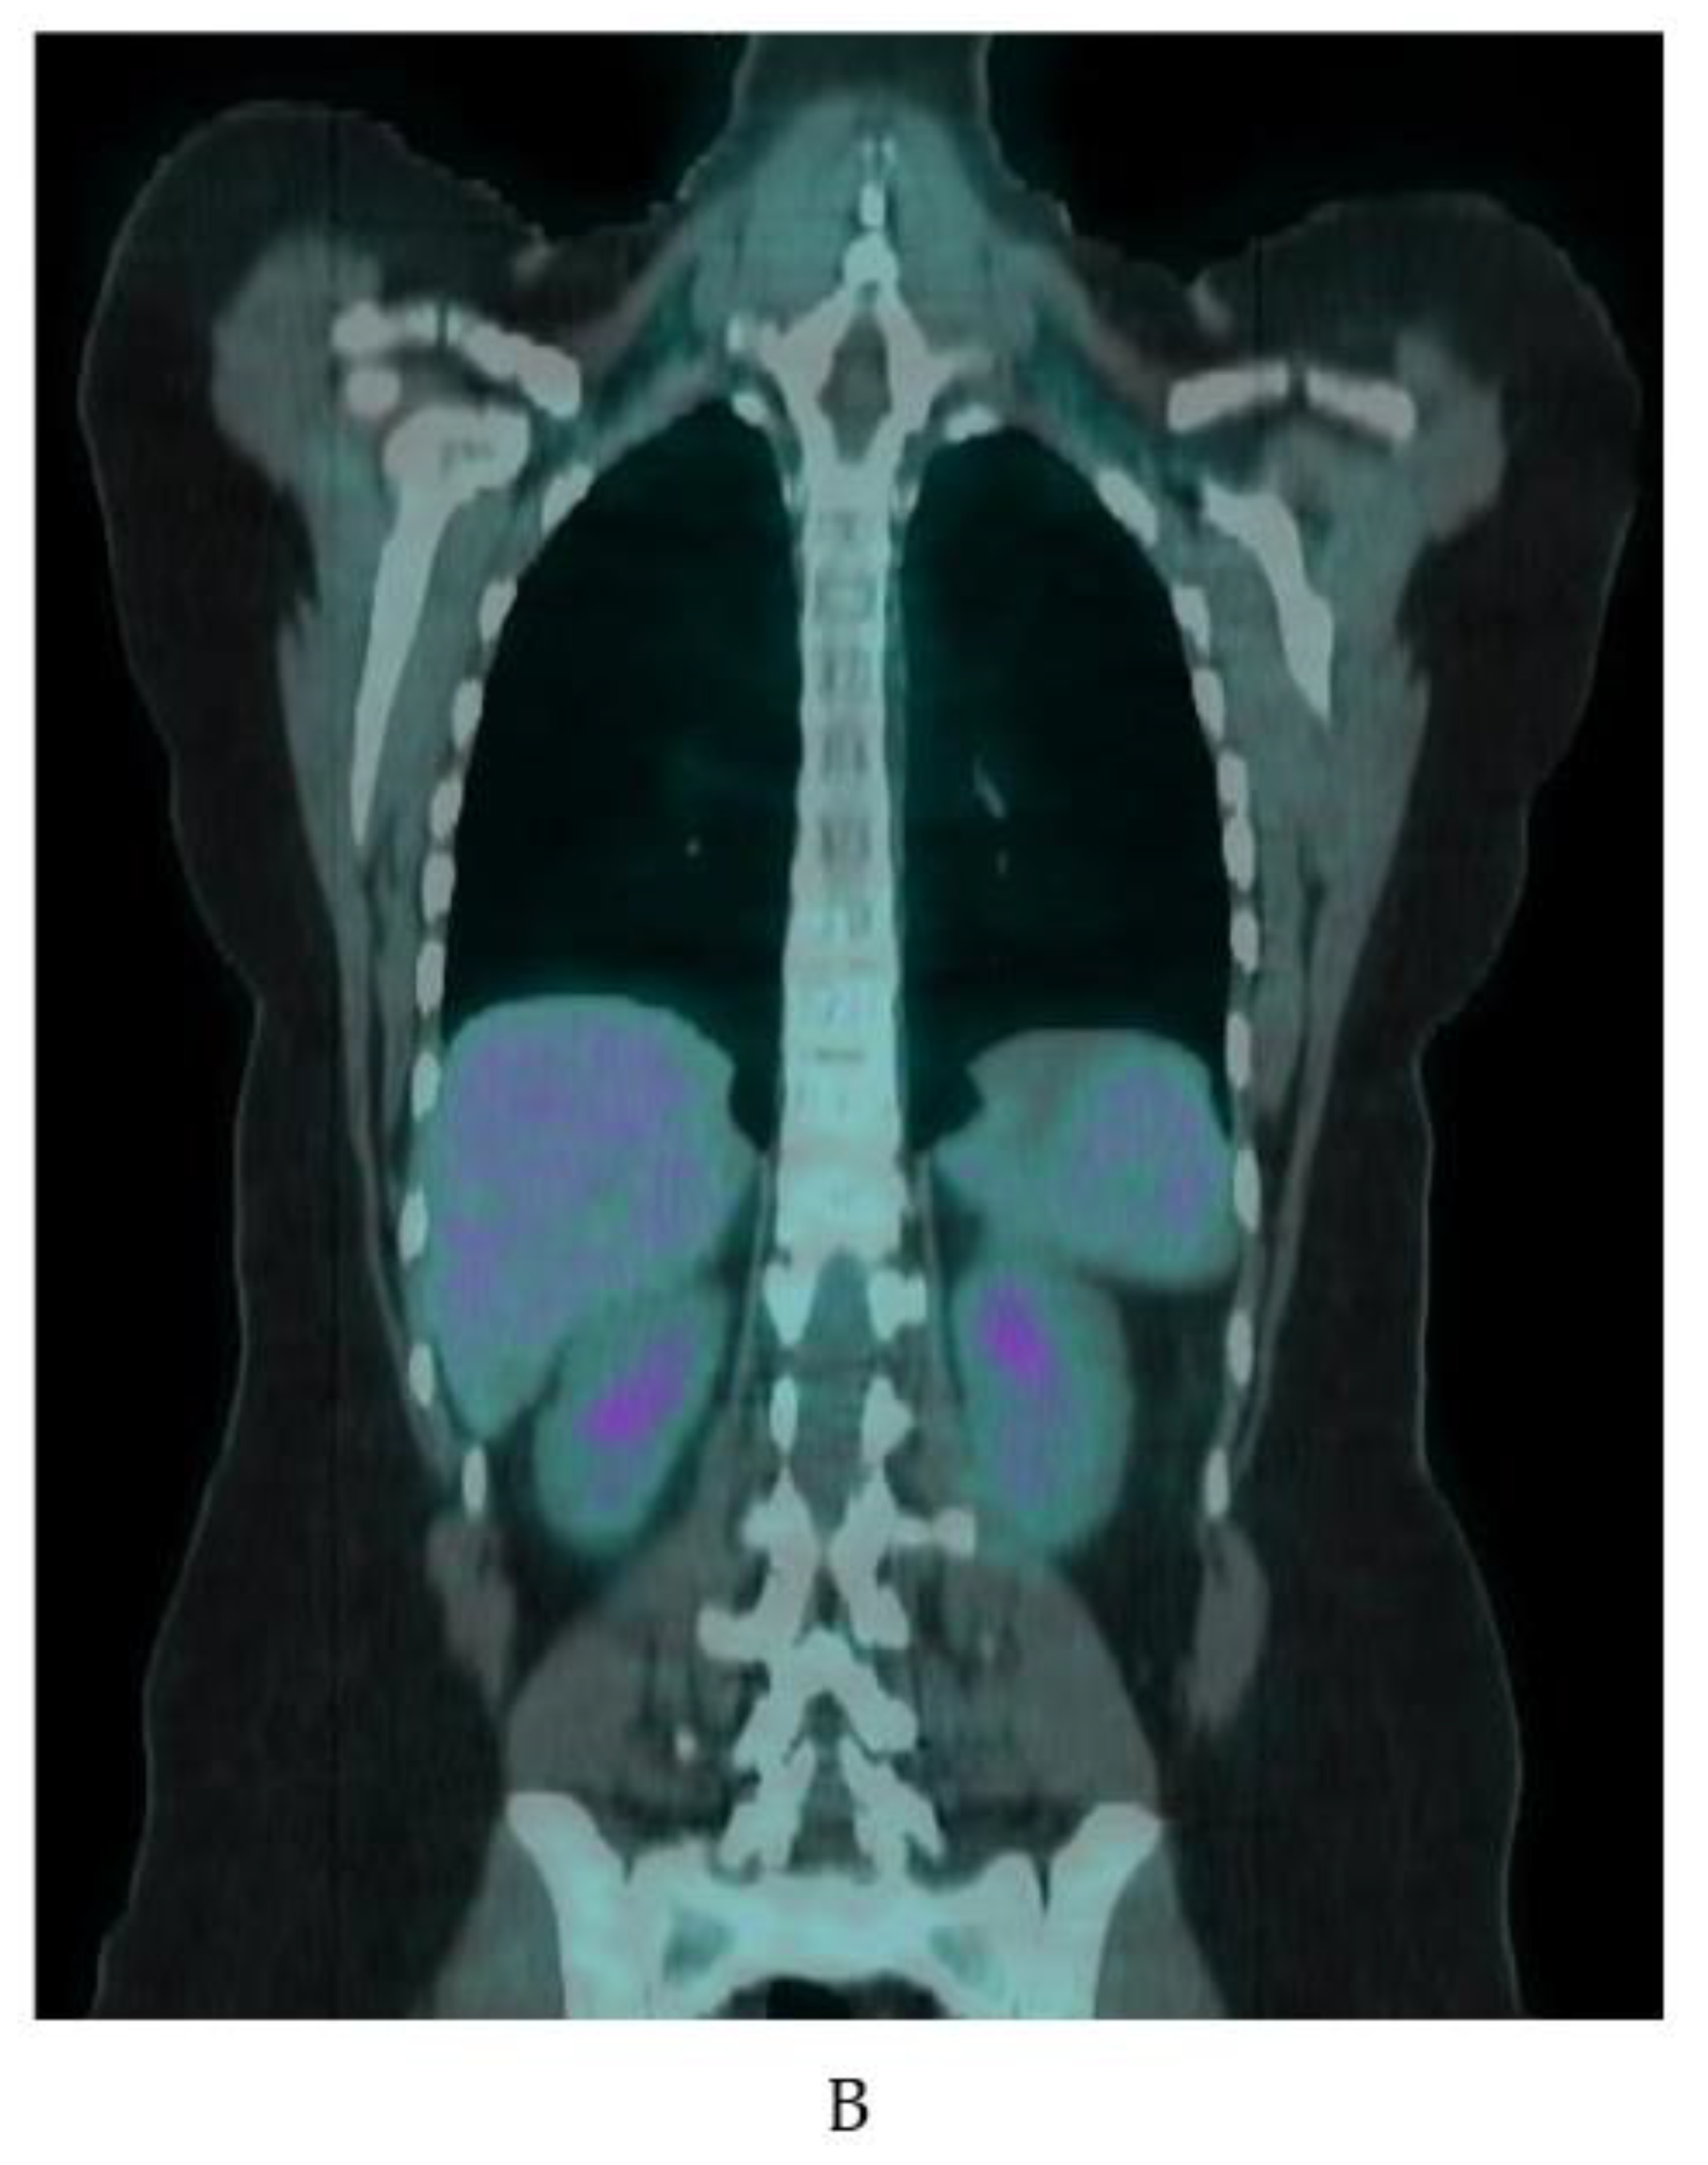

Prospective studies often use cooling protocols to induce iBAT activation. Leitner and colleagues showed a 20 min cold exposure is sufficient to activate iBAT in healthy adult volunteers [58]. In their study, 3 h of rewarming after cold exposure decreased FDG uptake by iBAT to near baseline [58]. Indeed, iBAT is so temperature sensitive a NIH expert panel recommends reporting outdoor temperature, season, and geographic location in any FDG-PET/CT study of iBAT [13]. Despite the strong association with cooler temperatures, we routinely see active iBAT on warm days in our large oncology practice where the uptake room is held at a constant temperature warm enough to prevent shivering. Figure 6 shows examples of the wide variation of uptake in clinical patients.

Figure 6.

Variation of BAT FDG uptake in clinical patients. Fused coronal FDG-PET/CT, coronal CT, and fused axial FDG-PET/CT (A–C). (A) BAT FDG uptake in a woman with normal BMI. Note supraclavicular (yellow arrows), skull base (red arrow), paraesophageal (blue arrow), and perinephric (white arrow) uptake. (B) Supraclavicular BAT in an obese woman (yellow arrows). (C) Diffuse FDG uptake in subcutaneous WAT in a male patient (yellow arrows). (D) A male patient with extensive supraclavicular FDG uptake extending into the upper neck (yellow arrows) and paravertebral BAT activity (blue arrows).